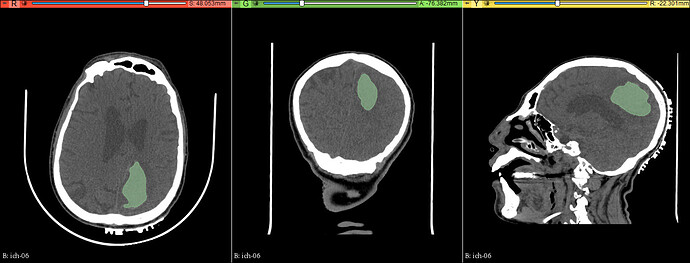

数据:005分割练习数据→脑出血→分水岭-顶叶脑出血定位帖

Watershed(分水岭)

• 应用笔刷或画笔涂画要分割的部分作为种子

• 换一种颜色涂画要分割组织的周围部分

• 点击预览观察分割结果是否正确

• 在错误的分割区域增加更多的种子,结果自动更新

• 可以定义结构的平滑度,从而可以防止泄漏